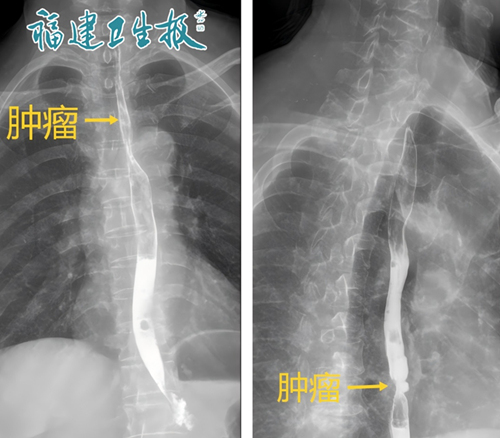

今年1月,泉州56岁的徐先生(化名)和妻子前往当地的医院体检。没想到,做胃肠镜时,夫妻俩都被查出了食管癌。幸运的是,夫妻俩发现及时,没有转移,尚属于早期。

▲夫妻俩都发现食管癌

夫妻俩来到福建省肿瘤医院。"我也就算了,我父亲当年也是得了食管癌,可能有基因遗传,但我妻子为什么这么年轻也得了这病?"徐先生非常不解。